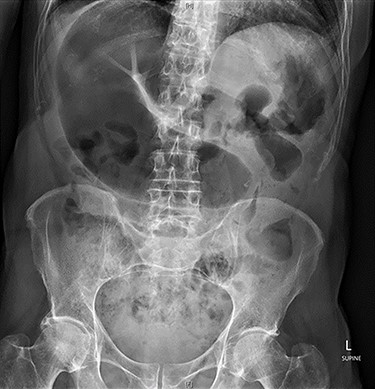

Abdominal X-ray revealed a grossly distended loop of colon with air-fluid levels, consistent with a large bowel obstruction (Fig. 1). A computed tomography (CT) scan demonstrated two transition points in the left colon with swirling of the mesentery, indicative of volvulus (Fig. 2). Following successful endoscopic decompression, the patient proceeded to laparoscopy and colopexy. The previous laparoscopic port sites were utilized. On table colonoscopy was performed during laparoscopy to allow delineation and decompression of the volvulus. As seen in Fig. 3A, the neo-left colon travelled behind the transverse colon mesentery and formed an alpha-type loop. Adhesions fusing the transverse colon mesentery to the neo-left colon were divided to mobilize the colon and to assist in devolving the bowel (Video 1). Interrupted polypropylene sutures were then used to fix the neo-left colon to the posterior gastric wall (Fig. 3B) and the left lateral abdominal wall (Fig. 3C). The patient’s bowels opened on postoperative Day 3 and he was discharged on postoperative Day 6. The patient remained well at 6 months follow-up with no further episodes of volvulus.

Abdominal X-ray on presentation showing a distended loop of colon with air-fluid levels.